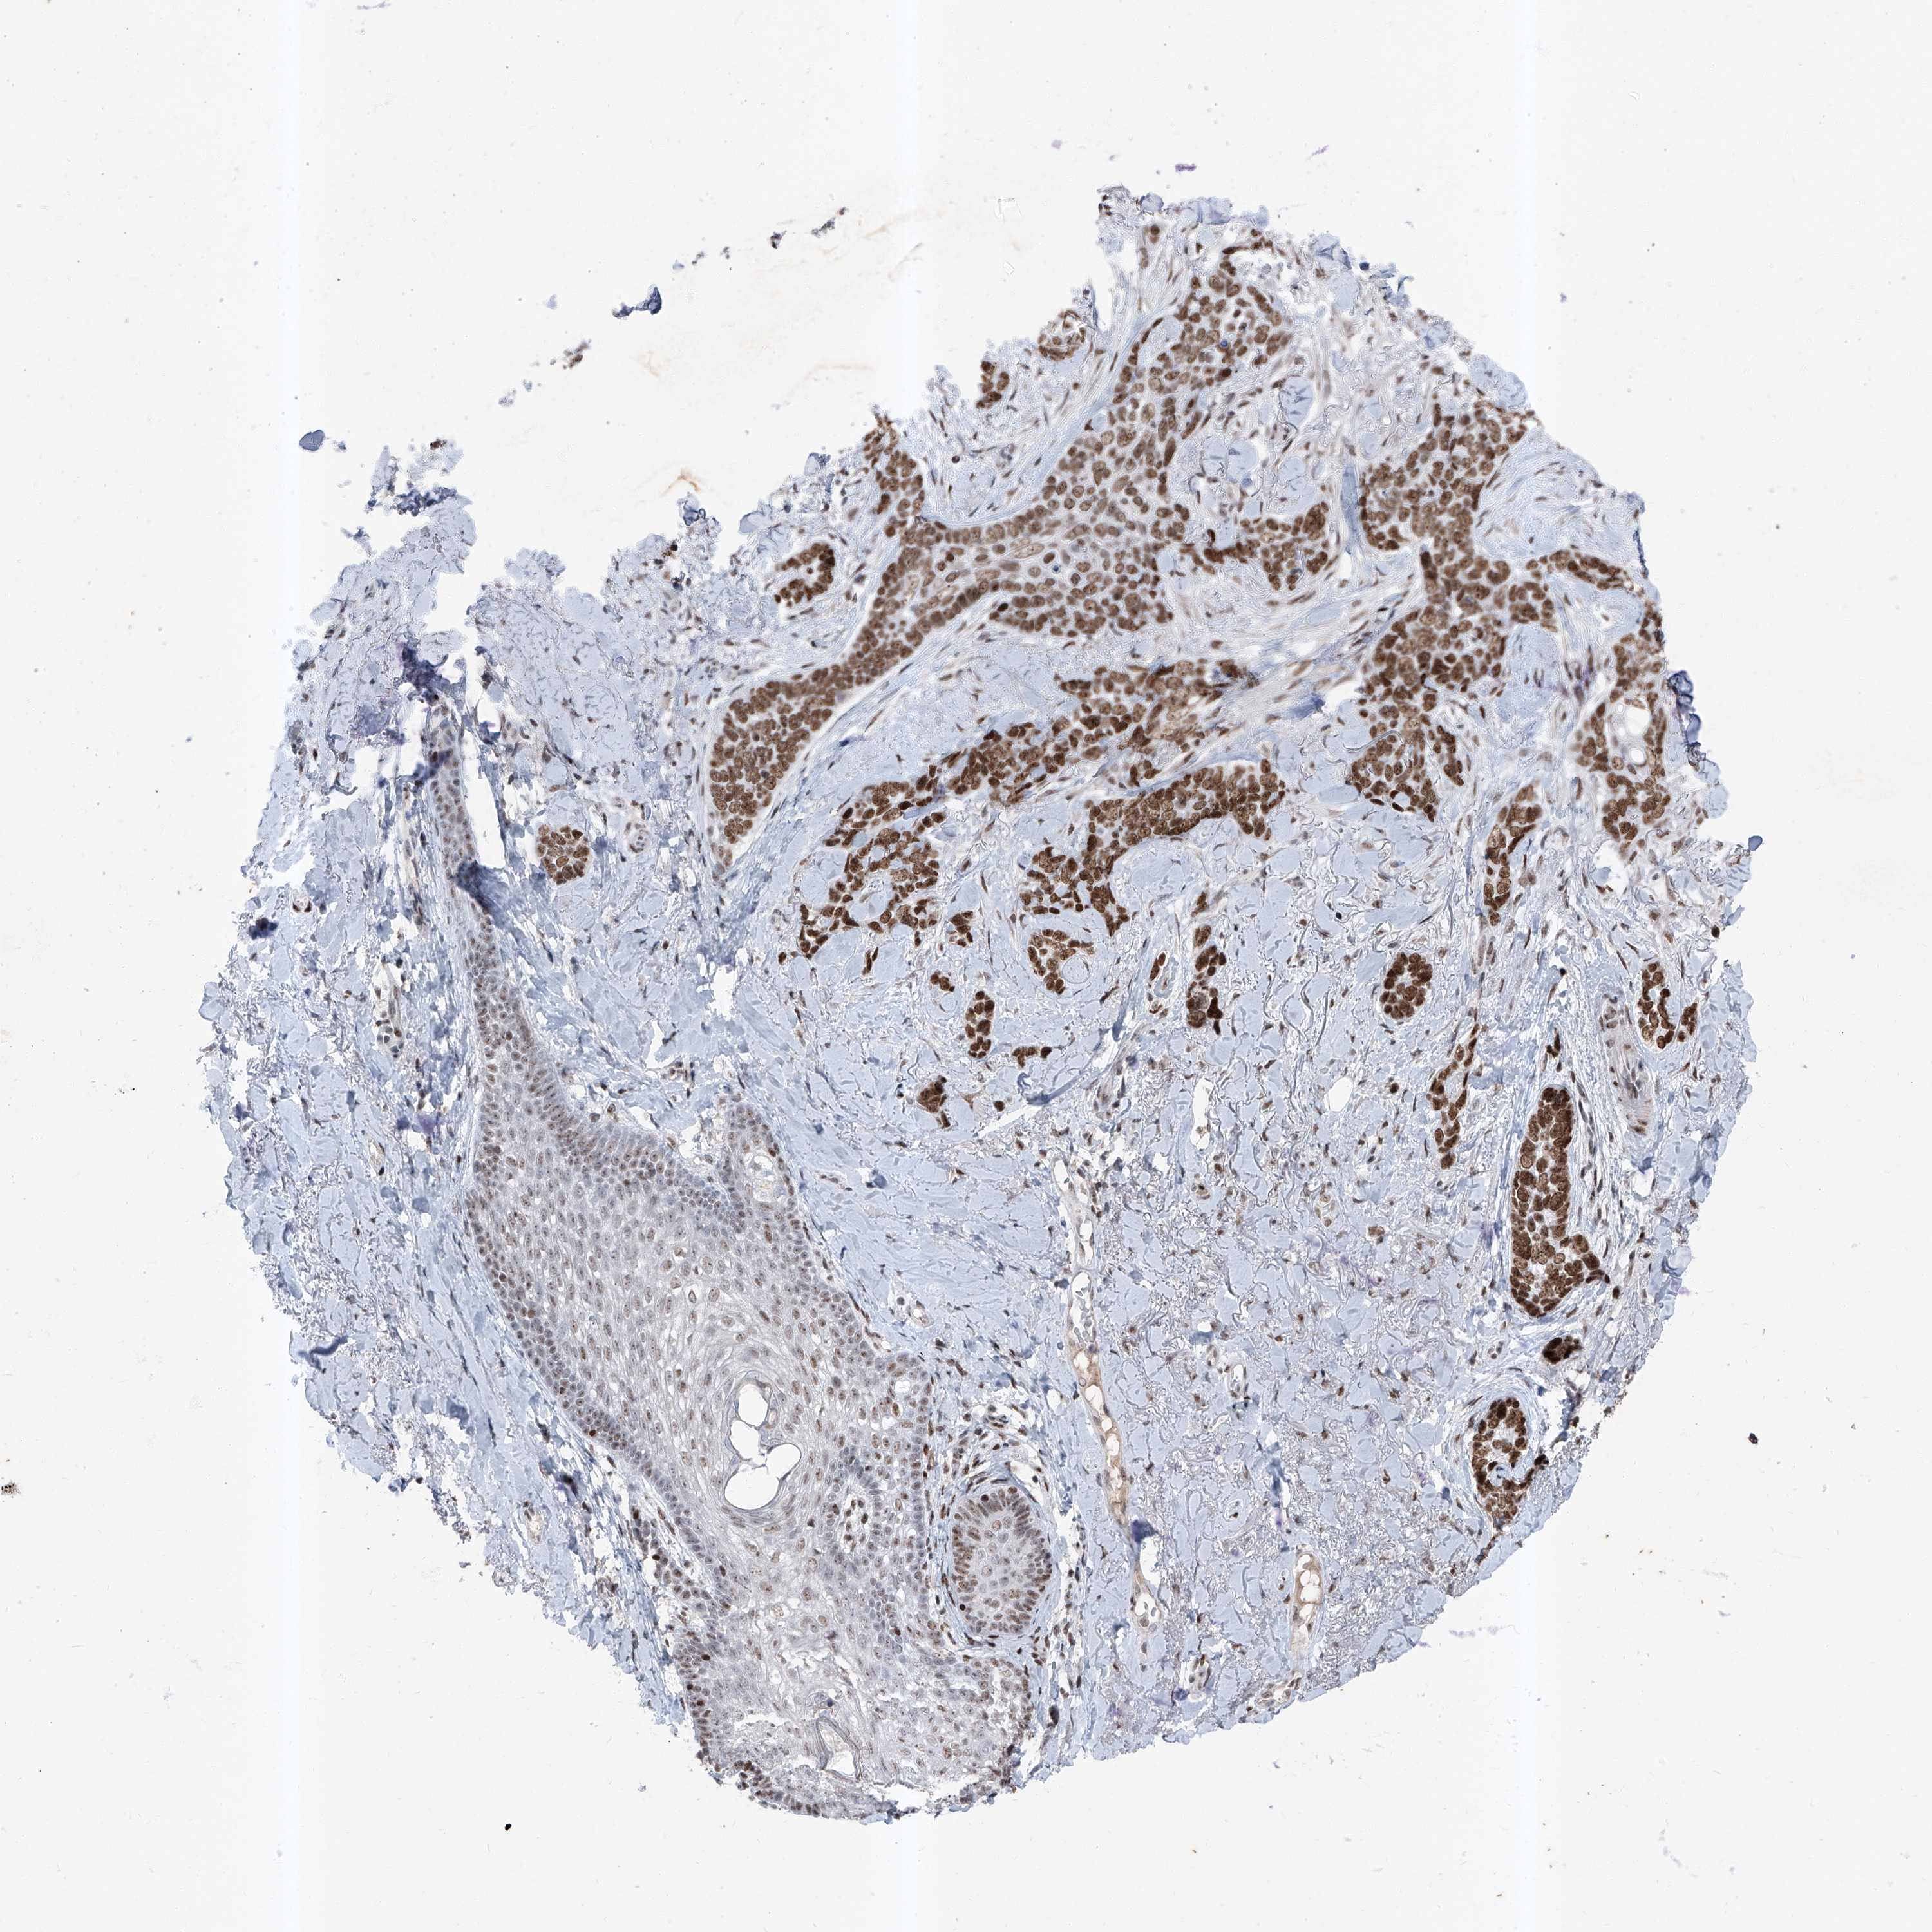

SKIN CANCER - Protein expressioni

A mouse-over function shows sample information and annotation data. Click on an image to view it in a full screen mode. Samples can be filtered based on level of antibody staining by selecting one or several of the following categories: high, medium, low and not detected. The assay and annotation is described here.

Antibody stainingi

Antibody staining in the annotated cell types in the current human tissue is reported as not detected, low, medium, or high, based on conventional immunohistochemistry profiling in selected tissues. This score is based on the combination of the staining intensity and fraction of stained cells.

Each image is clickable and will lead to virtual microscopy that enables deeper exploration of all samples and also displays staining intensity scores, fraction scores and subcellular localization as well as patient and tissue information for each sample.

Antibody HPA030472

Antibody HPA036584

Squamous cell carcinoma, NOS